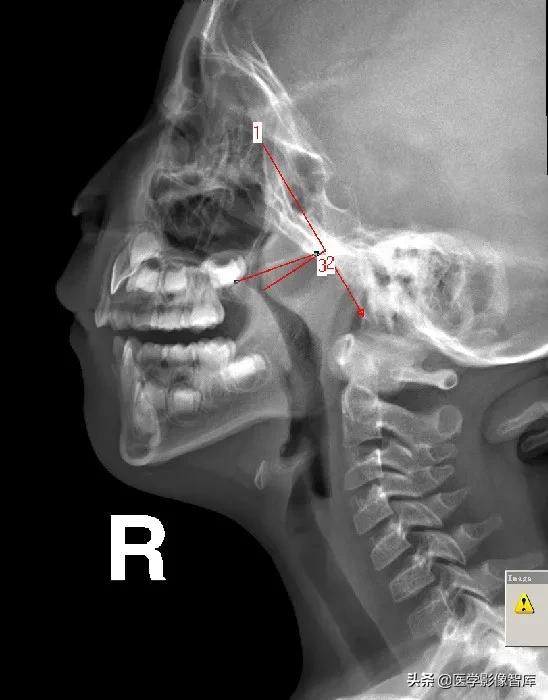

腺样体长度的测量

- 使用平行曲线法,沿C3椎体前软组织前缘向上划与颈椎相平行的直线,上行至软腭后下缘,水平转折向前向上划与软腭后上缘平行的弧线至硬腭后部,此线与突入鼻咽腔的腺样体后、前缘相交为b、a两点,ab间距为腺样体长径。

- 临床上应用较少。